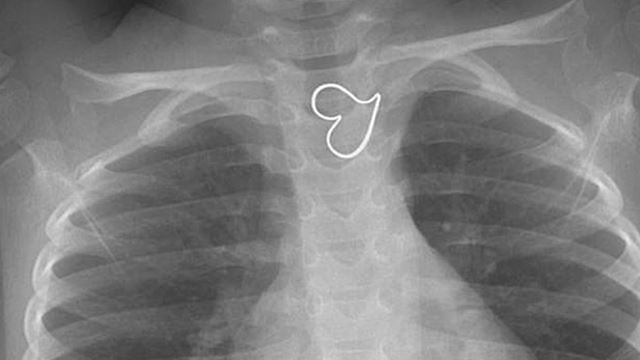

Doktor Jumpa Logo Hati Pada Dada Budak 3 Tahun Lepas Buat X-Ray